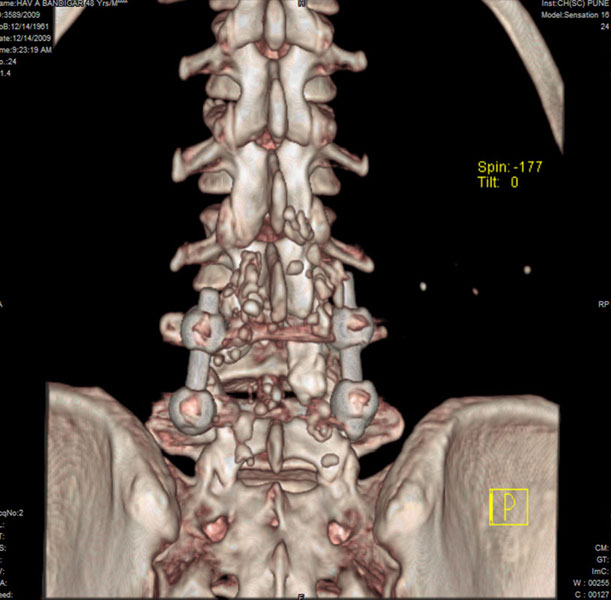

Spondylolisthesis malformations

Spondylolisthesis implies slippage of one lumbar vertebra over the next one, causing pain and nerve compression. Patient can also have difficulty in walking and numbness of the legs. Usually these patients need evaluation lumbar spine by MRI and CT scan, followed by spinal instrumentation and fusion.